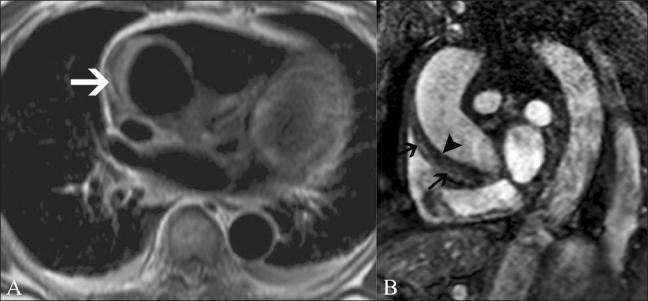

磁共振成像在评估心电图ST段抬高患者中的应用价值。

Utility of magnetic resonance imaging in the evaluation of patients with ST segment elevation on an electrocardiogram.

ST segment elevation is an important electrocardiographic (ECG) change that is typically found in acute myocardial infarction, but may also be seen in a variety of other conditions. MRI plays an important role in the evaluation of these patients. MRI not only establishes the diagnosis, which is essential for appropriate management, but also helps in the assessment of other factors that are important for risk stratification. In this review, we discuss the common and uncommon causes of ST segment elevation and the role of MRI in the evaluation of these disease processes.

摘要